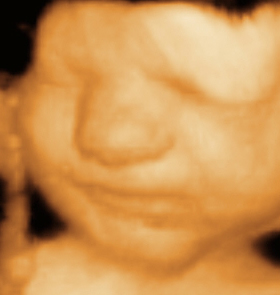

Bebeğin yüzü insan görünümündedir, ağız içinde ise üst damak birleşmeye başlamıştır. Yüz derisi içinde kıl kökleri belirmeye başlar. Ellerde ve ayaklarda tırnaklar uzamaya başlar. Bu haftada bebeğin bütün iç organları çalışır durumdadır. Çişini yapabilir. Tırnaklar gelişir. Bu haftadan sonra bebeğinizin ilaçlardan ve zararlı etkenlerden zarar görme olasılığı azalır. Cinsel organları cinsiyetini ortaya koyacak kadar gelişmiştir. Ancak ultrasonda bu ayrımı yapmak mümkün olabilir, ancak yanılma payı yüksektir. Boy:8 cm, Ağırlık: 18 gr.

Baş-popo uzunluğu 6-8 cm kadardır. Baş vücuttan büyük veya vücut kadardır. Gözler birbirine daha yakın, görünüm gittikçe daha çok insana benzemektedir. Barsaklar karin içerisindeki normal yerlerine geçer. El ve ayak parmakları tamamen oluşmuş, eklemler çalışmaktadır. Dış cinsel organlar artık görünür hale gelmiştir.